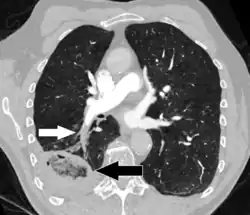

Lung infarction or pulmonary infarction occurs when an artery to the lung becomes blocked and part of the lung dies.[1] It is most often caused by a pulmonary embolism.

Because of the dual blood supply to the lungs from both the bronchial circulation and the pulmonary circulation, this tissue is more resistant to infarction. An occlusion of the bronchial circulation does not cause infarction, but it can still occur in pulmonary embolism when the pulmonary circulation is blocked and the bronchial circulation cannot fully compensate for it.[2]